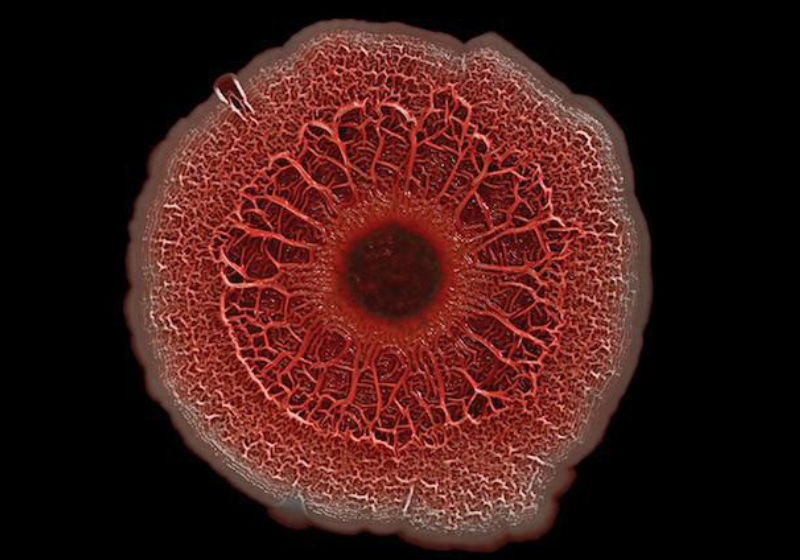

Uma colônia de milhões da bactéria Pseudomonas aeruginosa. Foto: NIH